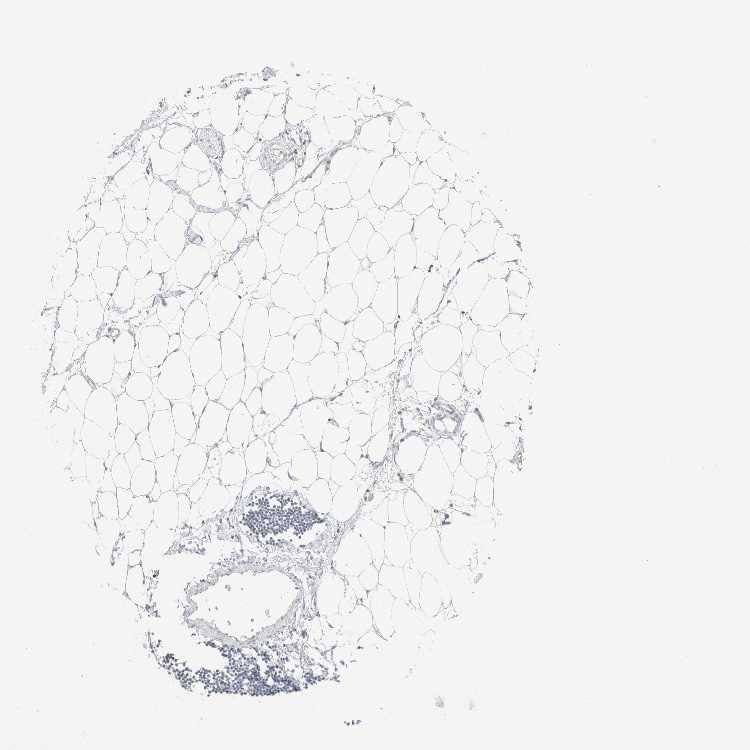

SOFT TISSUE 2 - Antibody stainingi

Antibody staining in the annotated cell types in the current human tissue is reported as not detected, low, medium, or high, based on conventional immunohistochemistry profiling in selected tissues. This score is based on the combination of the staining intensity and fraction of stained cells.

Each image is clickable and will lead to virtual microscopy that enables deeper exploration of all samples and also displays staining intensity scores, fraction scores and subcellular localization as well as patient and tissue information for each sample.

Antibody HPA021836Antibody HPA052215Antibody CAB025197

Fibroblasts Not detectedNot detectedNot detected

Peripheral nerve Not detectedNot detectedLow